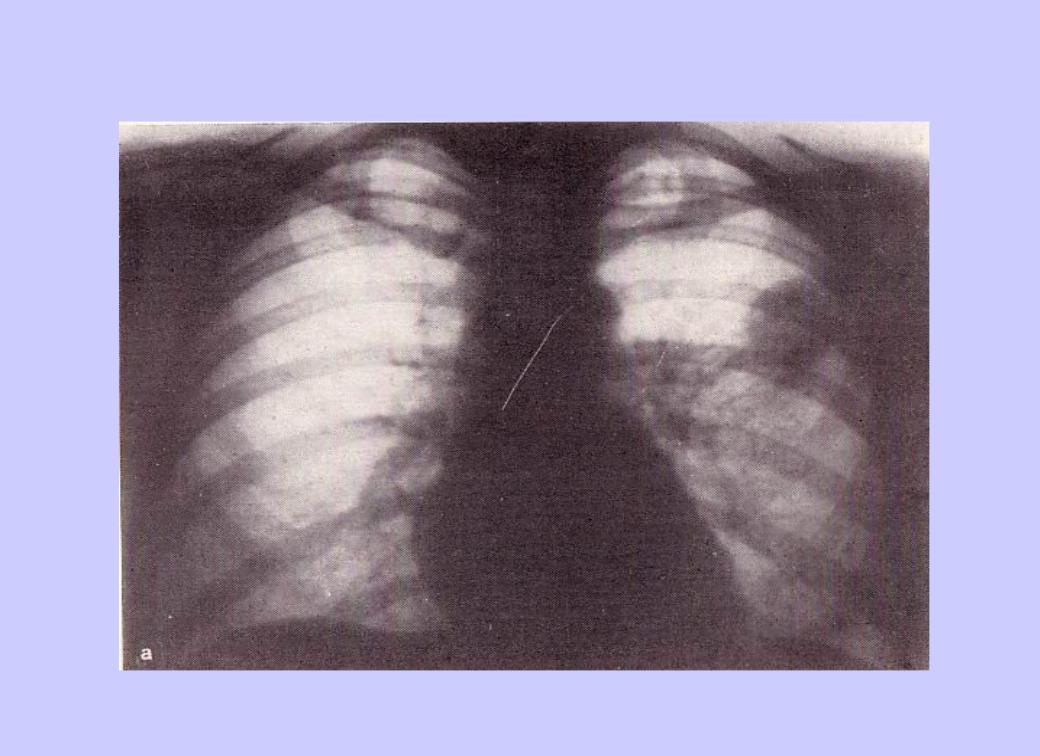

Иллюстрации по теме очагового и инфильтративного туберкулеза